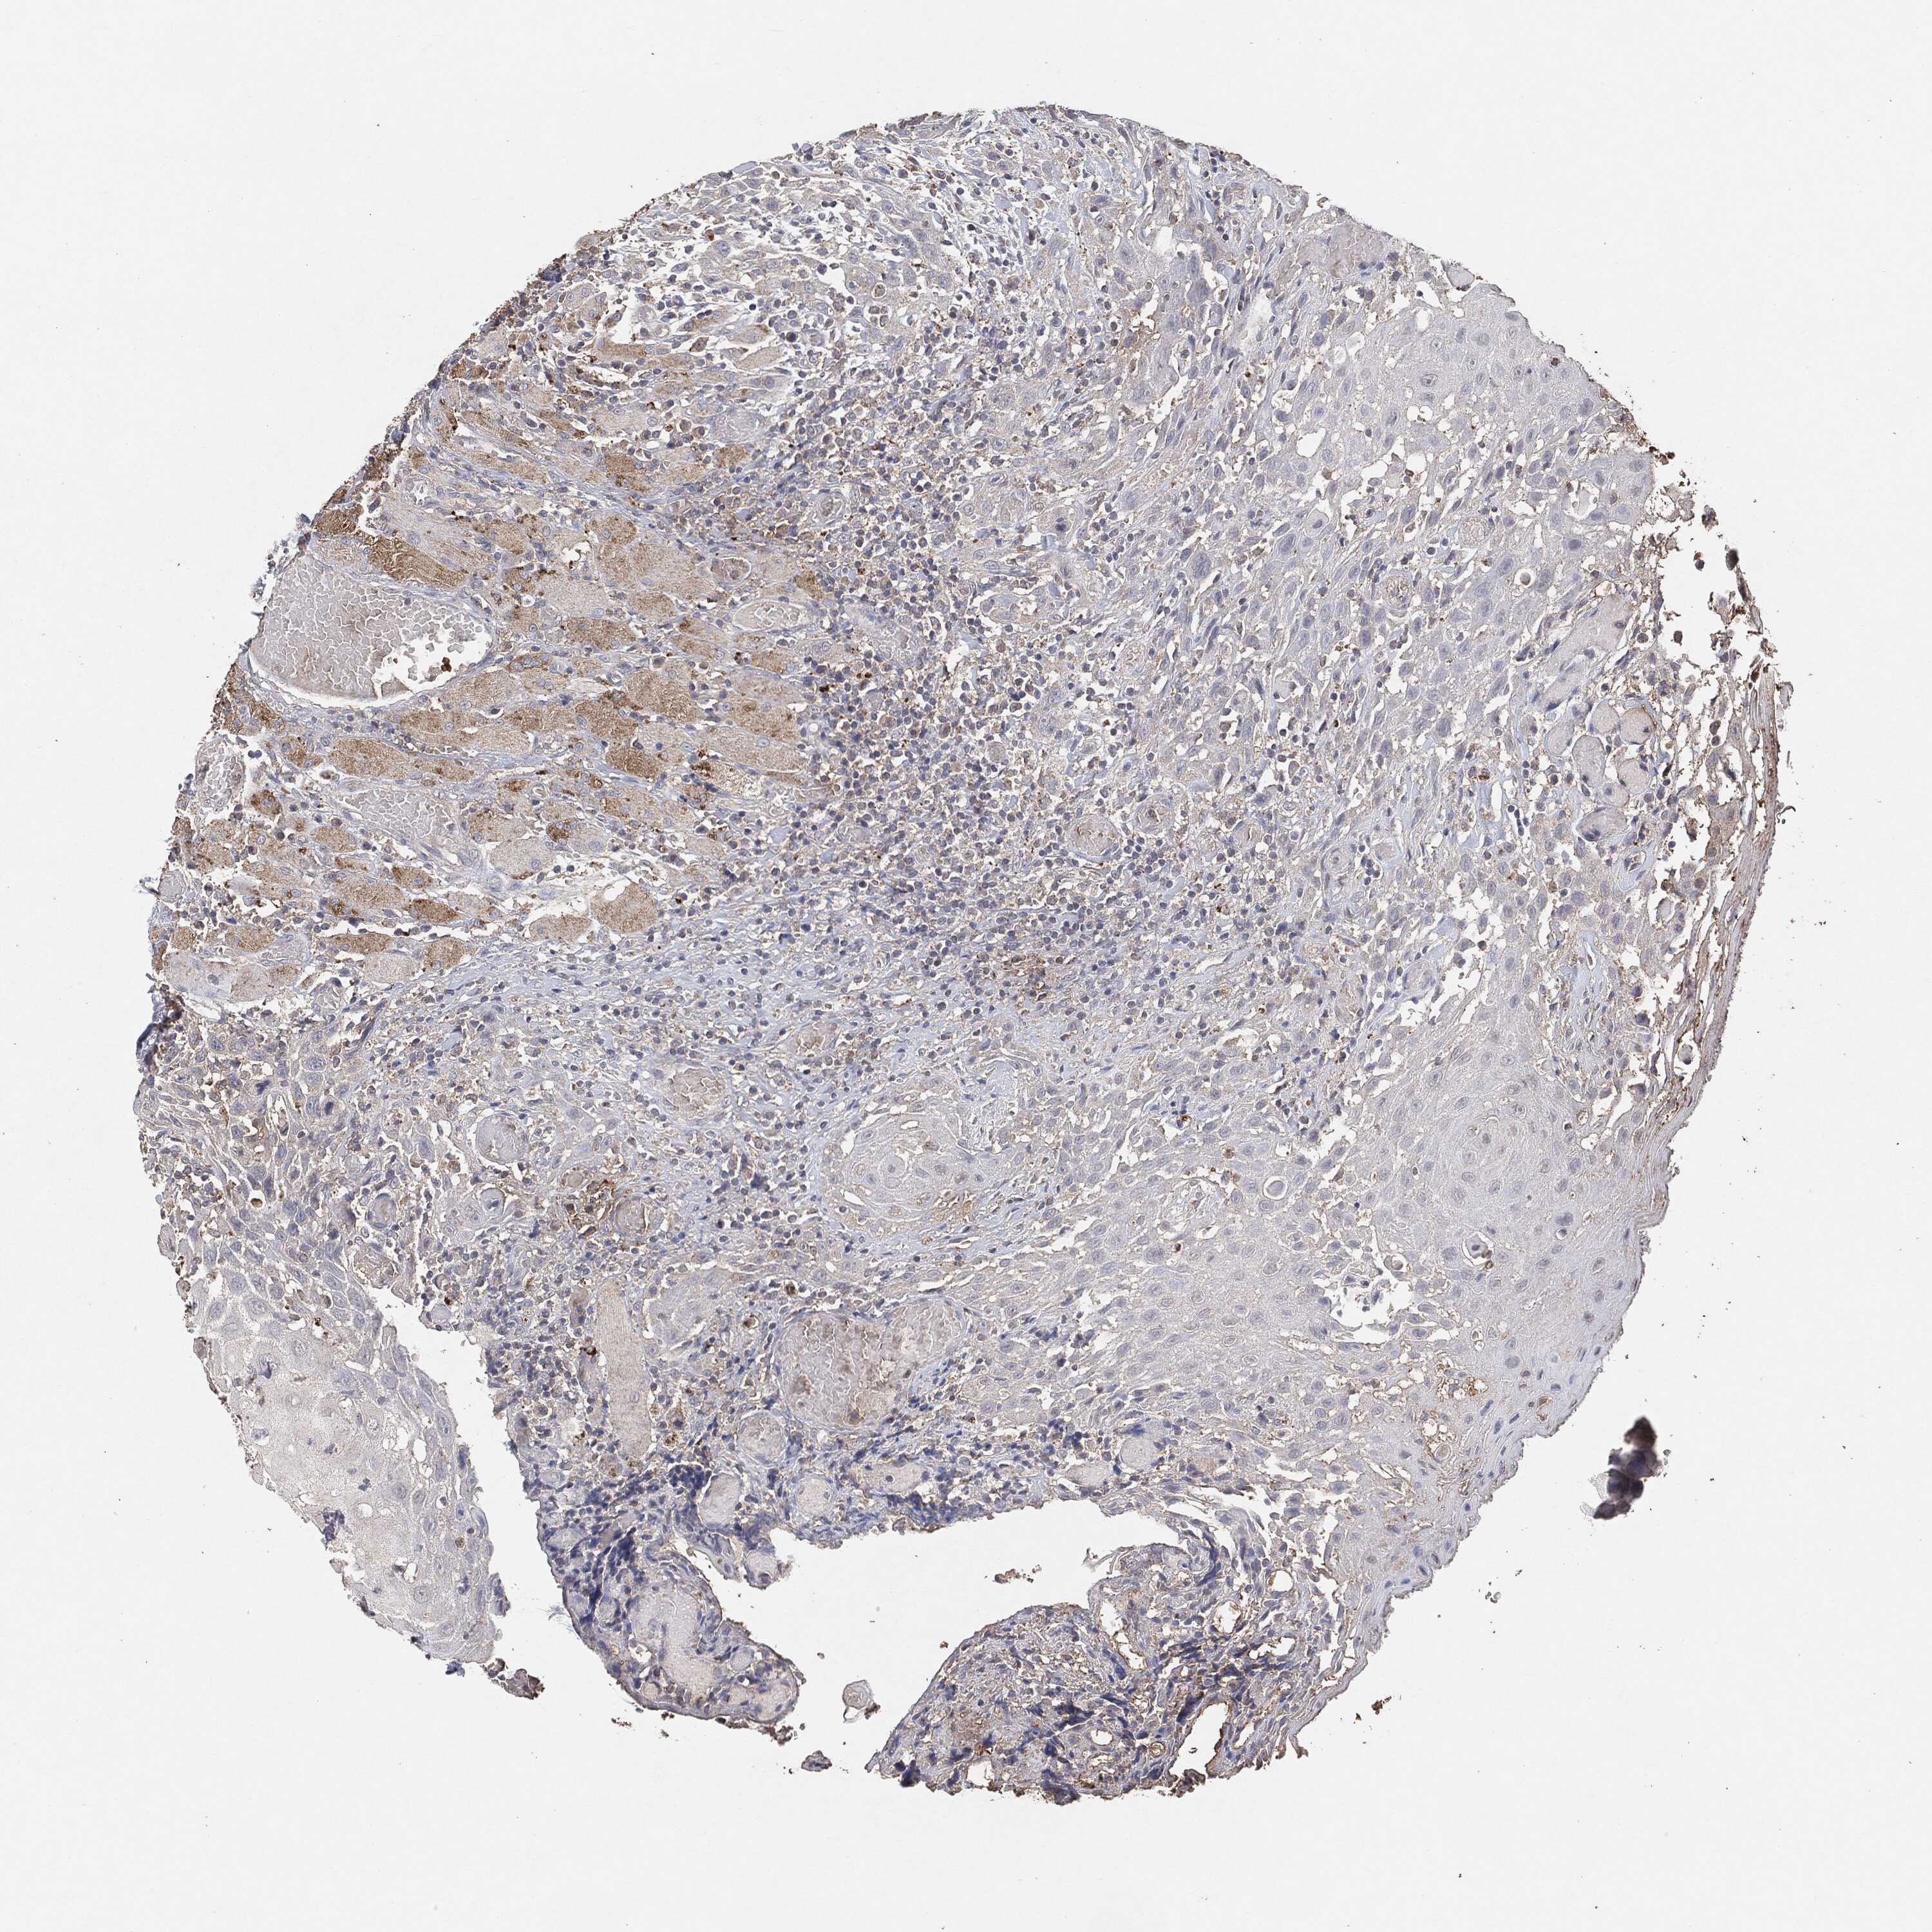

HEAD AND NECK CANCER - Protein expressioni

A mouse-over function shows sample information and annotation data. Click on an image to view it in a full screen mode. Samples can be filtered based on level of antibody staining by selecting one or several of the following categories: high, medium, low and not detected. The assay and annotation is described here.

Antibody stainingi

Antibody staining in the annotated cell types in the current human tissue is reported as not detected, low, medium, or high, based on conventional immunohistochemistry profiling in selected tissues. This score is based on the combination of the staining intensity and fraction of stained cells.

Each image is clickable and will lead to virtual microscopy that enables deeper exploration of all samples and also displays staining intensity scores, fraction scores and subcellular localization as well as patient and tissue information for each sample.